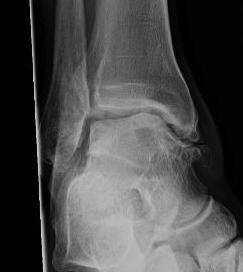

Xray

Ranges from anterior spurring to severe OA

80% of post-traumatic OA is varus

Takakura classification

| 1 | Early sclerosis and formation of osteophytes |

| 2 | Narrowing of the medial joint space |

| 3A | Obliteration of the medial joint space with subcondral bone contact |

| 3B | Obliteration of joint space over roof of talar dome, with subchondral bone contact |

| 4 | Obliteration of joint space with complete tibiotalar contact |

Type 1: Anterior spurs

Type 3A: Obliteration of medial joint space Type 3B: Obliteration medial joint space plus tibio-talar contact with varus

Type 4 complete obliteration